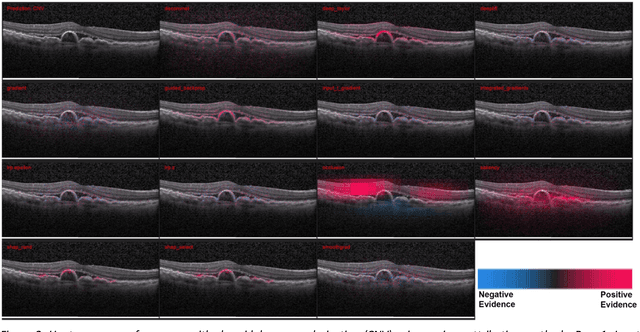

Abstract:Background: The lack of explanations for the decisions made by algorithms such as deep learning has hampered their acceptance by the clinical community despite highly accurate results on multiple problems. Recently, attribution methods have emerged for explaining deep learning models, and they have been tested on medical imaging problems. The performance of attribution methods is compared on standard machine learning datasets and not on medical images. In this study, we perform a comparative analysis to determine the most suitable explainability method for retinal OCT diagnosis. Methods: A commonly used deep learning model known as Inception v3 was trained to diagnose 3 retinal diseases - choroidal neovascularization (CNV), diabetic macular edema (DME), and drusen. The explanations from 13 different attribution methods were rated by a panel of 14 clinicians for clinical significance. Feedback was obtained from the clinicians regarding the current and future scope of such methods. Results: An attribution method based on a Taylor series expansion, called Deep Taylor was rated the highest by clinicians with a median rating of 3.85/5. It was followed by two other attribution methods, Guided backpropagation and SHAP (SHapley Additive exPlanations). Conclusion: Explanations of deep learning models can make them more transparent for clinical diagnosis. This study compared different explanations methods in the context of retinal OCT diagnosis and found that the best performing method may not be the one considered best for other deep learning tasks. Overall, there was a high degree of acceptance from the clinicians surveyed in the study. Keywords: explainable AI, deep learning, machine learning, image processing, Optical coherence tomography, retina, Diabetic macular edema, Choroidal Neovascularization, Drusen